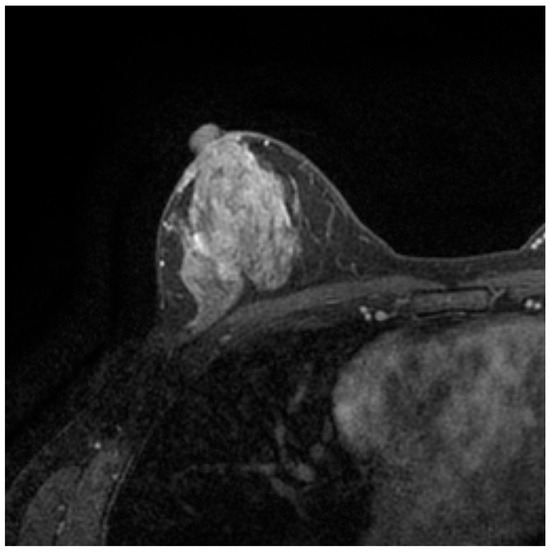

Advances in Medical Image Processing for Early Breast Cancer Detection: Classical Techniques and Deep Learning Perspectives

Breast cancer is the most common malignancy among women and a leading cause of cancer-related mortality, making early and accurate detection essential. This review summarises advances in breast imaging and computational diagnostics across mammography, ultrasound, and magnetic resonance imaging (MRI), highlighting challenges in differentiating benign from malignant lesions and identifying rarer tumour types. Key preprocessing steps—denoising, deblurring, and contrast enhancement—are reviewed as they improve image quality prior to analysis. Classical methods (e.g., thresholding, edge detection, and region growing) are compared with deep learning approaches for segmentation and classification. CNNs, RNNs, and emerging transformer-based models consistently outperform handcrafted pipelines, with representative studies reporting 5–15% gains in AUC/accuracy and deep models achieving AUC > 0.85–0.95 on several benchmarks. The review also discusses dataset constraints, common evaluation metrics (AUC, Dice, sensitivity, specificity), and clinical translation barriers such as interpretability and domain shift. Overall, AI-driven methods show strong potential to enhance early detection and support improved breast cancer outcomes. Full article

Show Figures

Figure 1